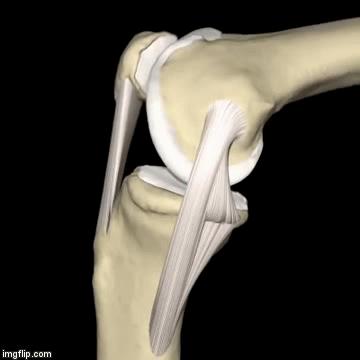

很多人的认识当中,我们的膝关节是一个关节,但在专业医生眼里,我们的膝关节是有两个股骨-胫骨间室以及髌骨-股骨间室三个关节共同构成的。而髌骨软骨软化主要是发生在髌骨-股骨间室这个关节。大家看下面这两个动图可以更好的理解在髌骨的活动轨迹以及特点,在关节屈伸过程当中,随着屈膝角度的加大,髌骨与后方的股骨接触会越来越紧密,压力也会越来越大,另外在正常屈伸关节的时候,髌骨的活动轨迹不应该有倾斜的。

所谓的髌骨软骨软化可不是软骨变软了,而是软骨磨损了。导致髌骨软骨软磨损的原因有很多,比如长时间的过度使用,长时间的蹲着,长时间的反复做关节的扭转动作、髌骨先天发育异常以及体重、遗传等因素。大家可以想一想,如果长时间的蹲着,髌骨以及后方的股骨之间是一直在顶着的,这个压力始终持续的存在,非常容易导致软骨的磨损;另外如果因为某一些先天因素以及过度使用导致髌骨明显的向外侧倾斜,髌骨与其后方的股骨之间的压力也会越来越大,这也会造成软骨的磨损。